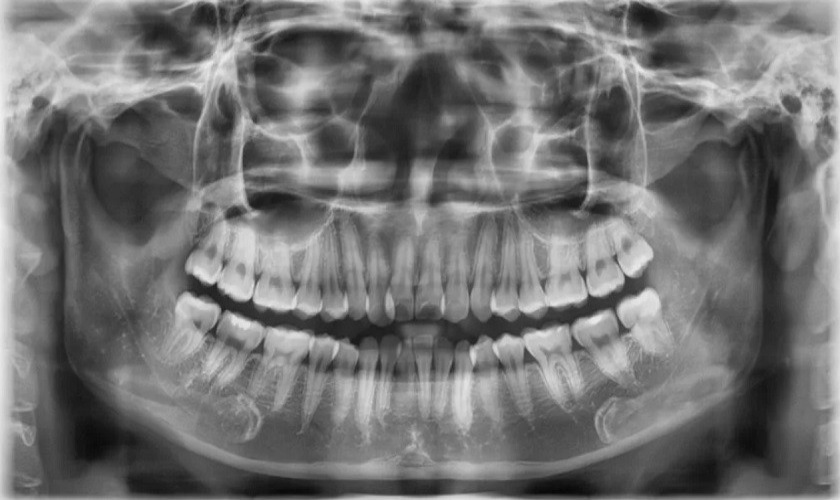

Chụp X-quang kiểm tra tại cơ sở nha khoa sau phẫu thuật

Chụp X-quang kiểm tra tại cơ sở nha khoa sau phẫu thuật là một bước quan trọng để đảm bảo rằng quá trình nhổ răng khôn đã diễn ra một cách toàn diện và an toàn.

Kết quả của hình ảnh X-quang sẽ cung cấp cho bác sĩ một cái nhìn chi tiết về cấu trúc và vị trí của chân răng, giúp bác sĩ xác định có mảnh răng nào còn sót lại hay không.

Chụp X-quang giúp bác sĩ phát hiện ra được tình trạng nhổ răng khôn còn sót chân răng

Ngoài ra, hình ảnh thu được còn hỗ trợ bác sĩ phát hiện và xử lý mọi vấn đề tiềm ẩn. Nếu có bất kỳ chân răng nào bị bỏ sót trong quá trình nhổ răng khôn, chúng sẽ xuất hiện rõ ràng trên hình ảnh X-quang, cung cấp thông tin quan trọng để đưa ra quyết định về liệu pháp điều trị tiếp theo.

Chụp X - quang kiểm tra tra các bệnh lý khác tại bệnh viện

Với trường hợp nhổ răng khôn còn sót chân răng bác sĩ thực hiện cũng không biết nhưng vô tình khách hàng đi chụp X-quang làm một điều trị khác lại vô tình phát hiện chân răng khôn còn sót lại.

Phim chụp X- Ray mang lại hình ảnh và thông tin rõ nét, chính xác